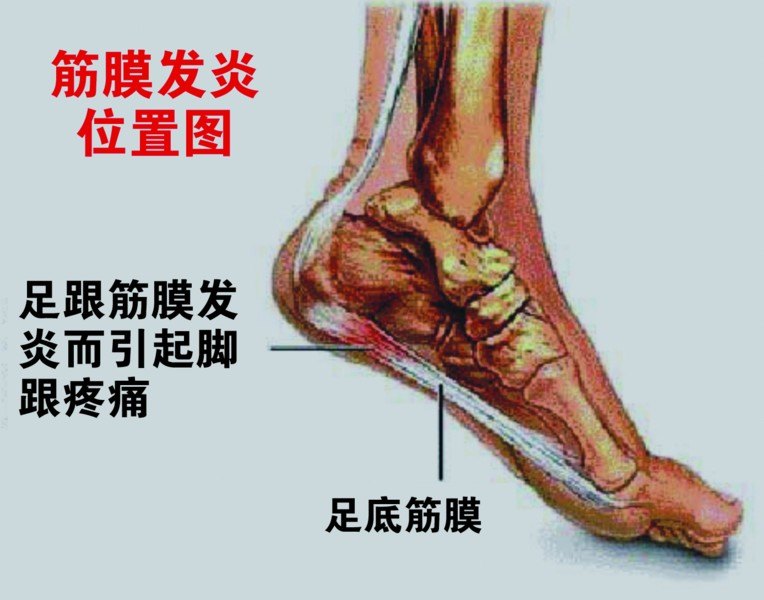

1,跖底筋膜炎

先来看看什么是跖底筋膜。

上图中白色的条索状的是肌腱和筋膜,其中位于脚底板的那一条就是跖底筋膜,红色的部位就是跖底筋膜的病变部位。所谓跖底筋膜炎,就是这条筋膜在脚后跟的止点处发炎了。实际上也并不全是因为炎症,更多时候是因为反复劳损、退变,引起的筋膜微小的撕裂口。

当我们走路抬起脚后跟时,前脚掌和地面接触并负重固定,后脚跟抬起,跖底筋膜被拉伸,天长日久,每天要走多少步,如此大量的反复的拉伸,逐渐导致了这条筋膜的病损。

跖底筋膜炎的疼痛位置一般在脚后跟的底部稍偏内,常常按压会有疼痛感,脚跟下面有固定的压痛点。